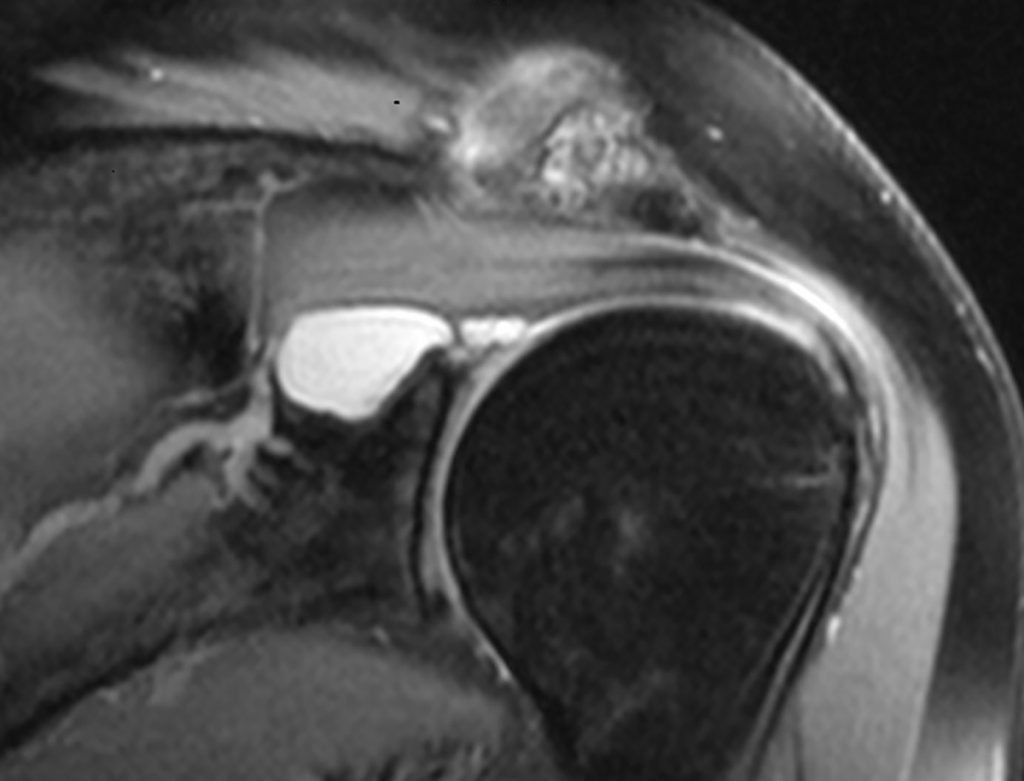

Frantzens funn er i samråd med hva overlege Khaled Meknas fant ut i sin lokale studie av MR-undersøkelser av skuldre i Tromsø:

– De ferskeste tallene jeg har fått tilgang til er fra 2014. Da ble det gjort 484 MR-undersøkelser av skuldre her på UNN Tromsø, hvor det er store kapasitetsproblemer på MR-maskinene. Så ble det i tillegg gjort 2.486 MR-undersøkelser av skuldre på en privat klinikk i Tromsø sentrum, den som nå er kjøpt opp av Aleris, forteller Meknas om resultater fra studien sin.

Av disse totalt 2.970 MR-undersøkelsene av vonde skuldre, fant han at 41 prosent av tilfellene var uten relevant indikasjon og at det i 49 prosent av tilfellene ikke var samsvar mellom klinisk diagnose og MR-funn. Satt på spissen betyr det altså at mellom 800 og 1.000 av MR-undersøkelsene var unødvendige.

– Nær sagt alle over 40 år vil oppleve at det er «noe» på et MR-bilde. De aller fleste kan da ha en liten artrose i skulderen, og det finnes en rekke andre naturlige tilstander som det ikke er noen plager med eller som trenger behandling, men som vil vises på et MR-bilde, sier Meknas.